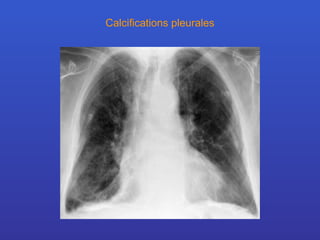

Calcifications pleurales

Syndromes radiologiques Calcifications

Définition: Les calcification sont plus facilement repérées sur des clichés faits en basse tension. Elles sont analysées en fonction de leur topographie. localisations calcifications pleurales calcifications cardio-vasculaires calcifications ganglionnaires calcifications trachéo-bronchiques calcifications au sein de masses médiastinales calcifications pulmonaires